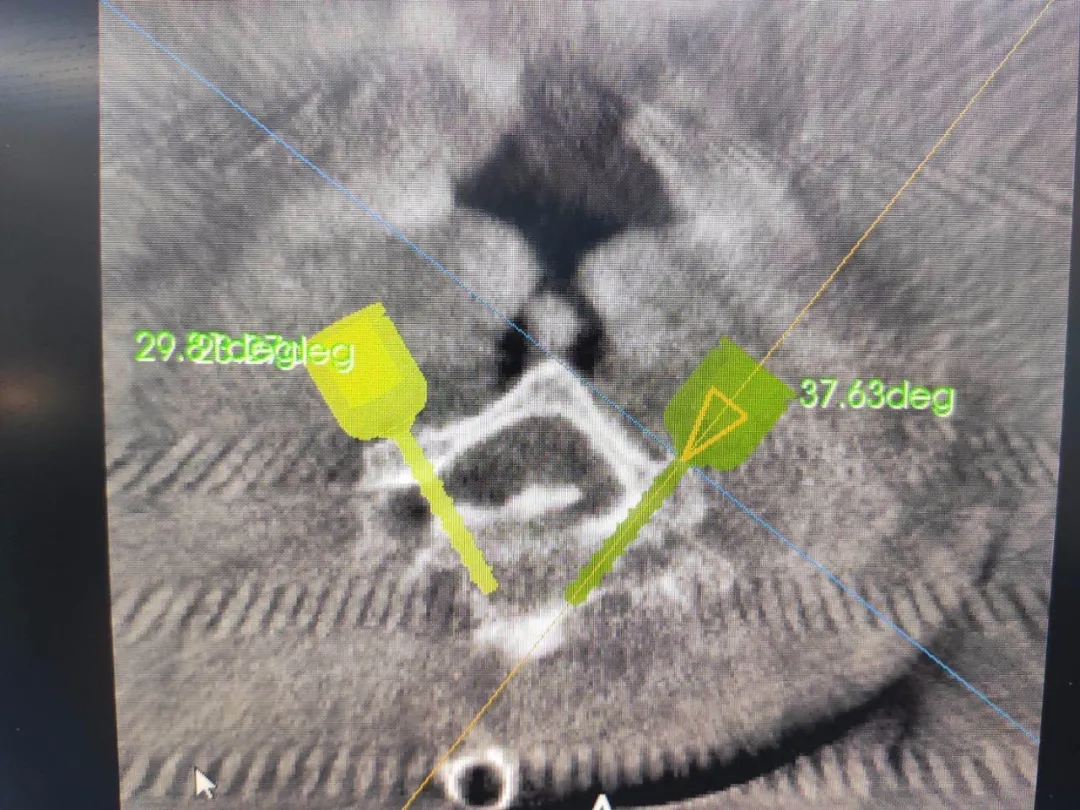

ÊõÖÐÔÚ°²ÅźÃÌå±í¶¨Î»ÒǺ󣬣¬£¬£¬£¬µÐÊÖÊõ²¿Î»¾ÙÐÐÈýάɨÃ裬£¬£¬£¬£¬ÍýÏë¾±7×µ¹¸ùÂݶ¤Öö¤õè¾¶¡£¡£¡£¡£¡£¡£¡£

¾±×µºó·ÊÖÊõÖ®ÒÔÊǽÏǰ·ÊÖÊõΣº¦¸üºÆ½Ù¶È½Ï¸ß£¬£¬£¬£¬£¬³ýÁËÌåÏÖÔÚ¼õѹʱÈÝÒ×ËðÉËÉñ¾Ö®Í⣬£¬£¬£¬£¬ÉÐÓÐÒ»¸öÖ÷ÒªµÄµã¼´ÊǾ±×µµÄ×µ¹¸ù½Ïϸ£¬£¬£¬£¬£¬Âݶ¤Ö²Èëʱ¹ØÓÚÖö¤µãºÍÖö¤½Ç¶ÈµÄÒªÇ󼫸ߣ¬£¬£¬£¬£¬ÉÔÓÐʧÉ÷¾Í»á·ºÆðÎó²î£¬£¬£¬£¬£¬ËðÉËÉñ¾¼°Ñª¹Ü£¬£¬£¬£¬£¬ÉõÖÁÓÚΣ¼°ÉúÃü£¬£¬£¬£¬£¬¶øÕâÖÖΣº¦ÔÚÓÐÁËÌìçá?¹Ç¿ÆÊÖÊõ»úеÈ˸¨Öúºó£¬£¬£¬£¬£¬½èÖúÌìçá?¹Ç¿ÆÊÖÊõ»úеÈ˾«×¼µÄ¶¨Î»¼°Ö¸µ¼£¬£¬£¬£¬£¬ÕâÖÖΣº¦¿É´ó´ó½µµÍ¡£¡£¡£¡£¡£¡£¡£